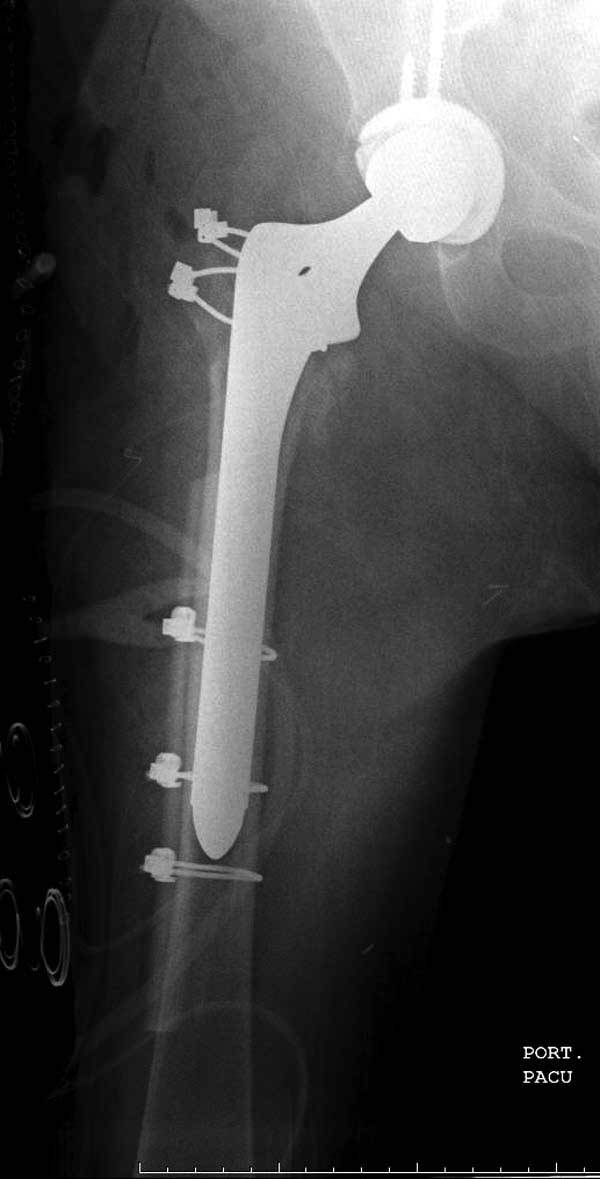

Такие “чужие осложнения” встречаются у всех и представляю банальный случай, который шаг за шагом показано как перерос в более сложный процесс... Больная 70 лет, множественные ко-морбидности, чрезвертельный перелом первоначально фиксирован Гамма 3. Осложнение в течение 6 недель, ревизия тотальной артропластикой и во время установки ножки обнаружена трещина диафиза (17), из малого доступа фиксация алло-графтом.